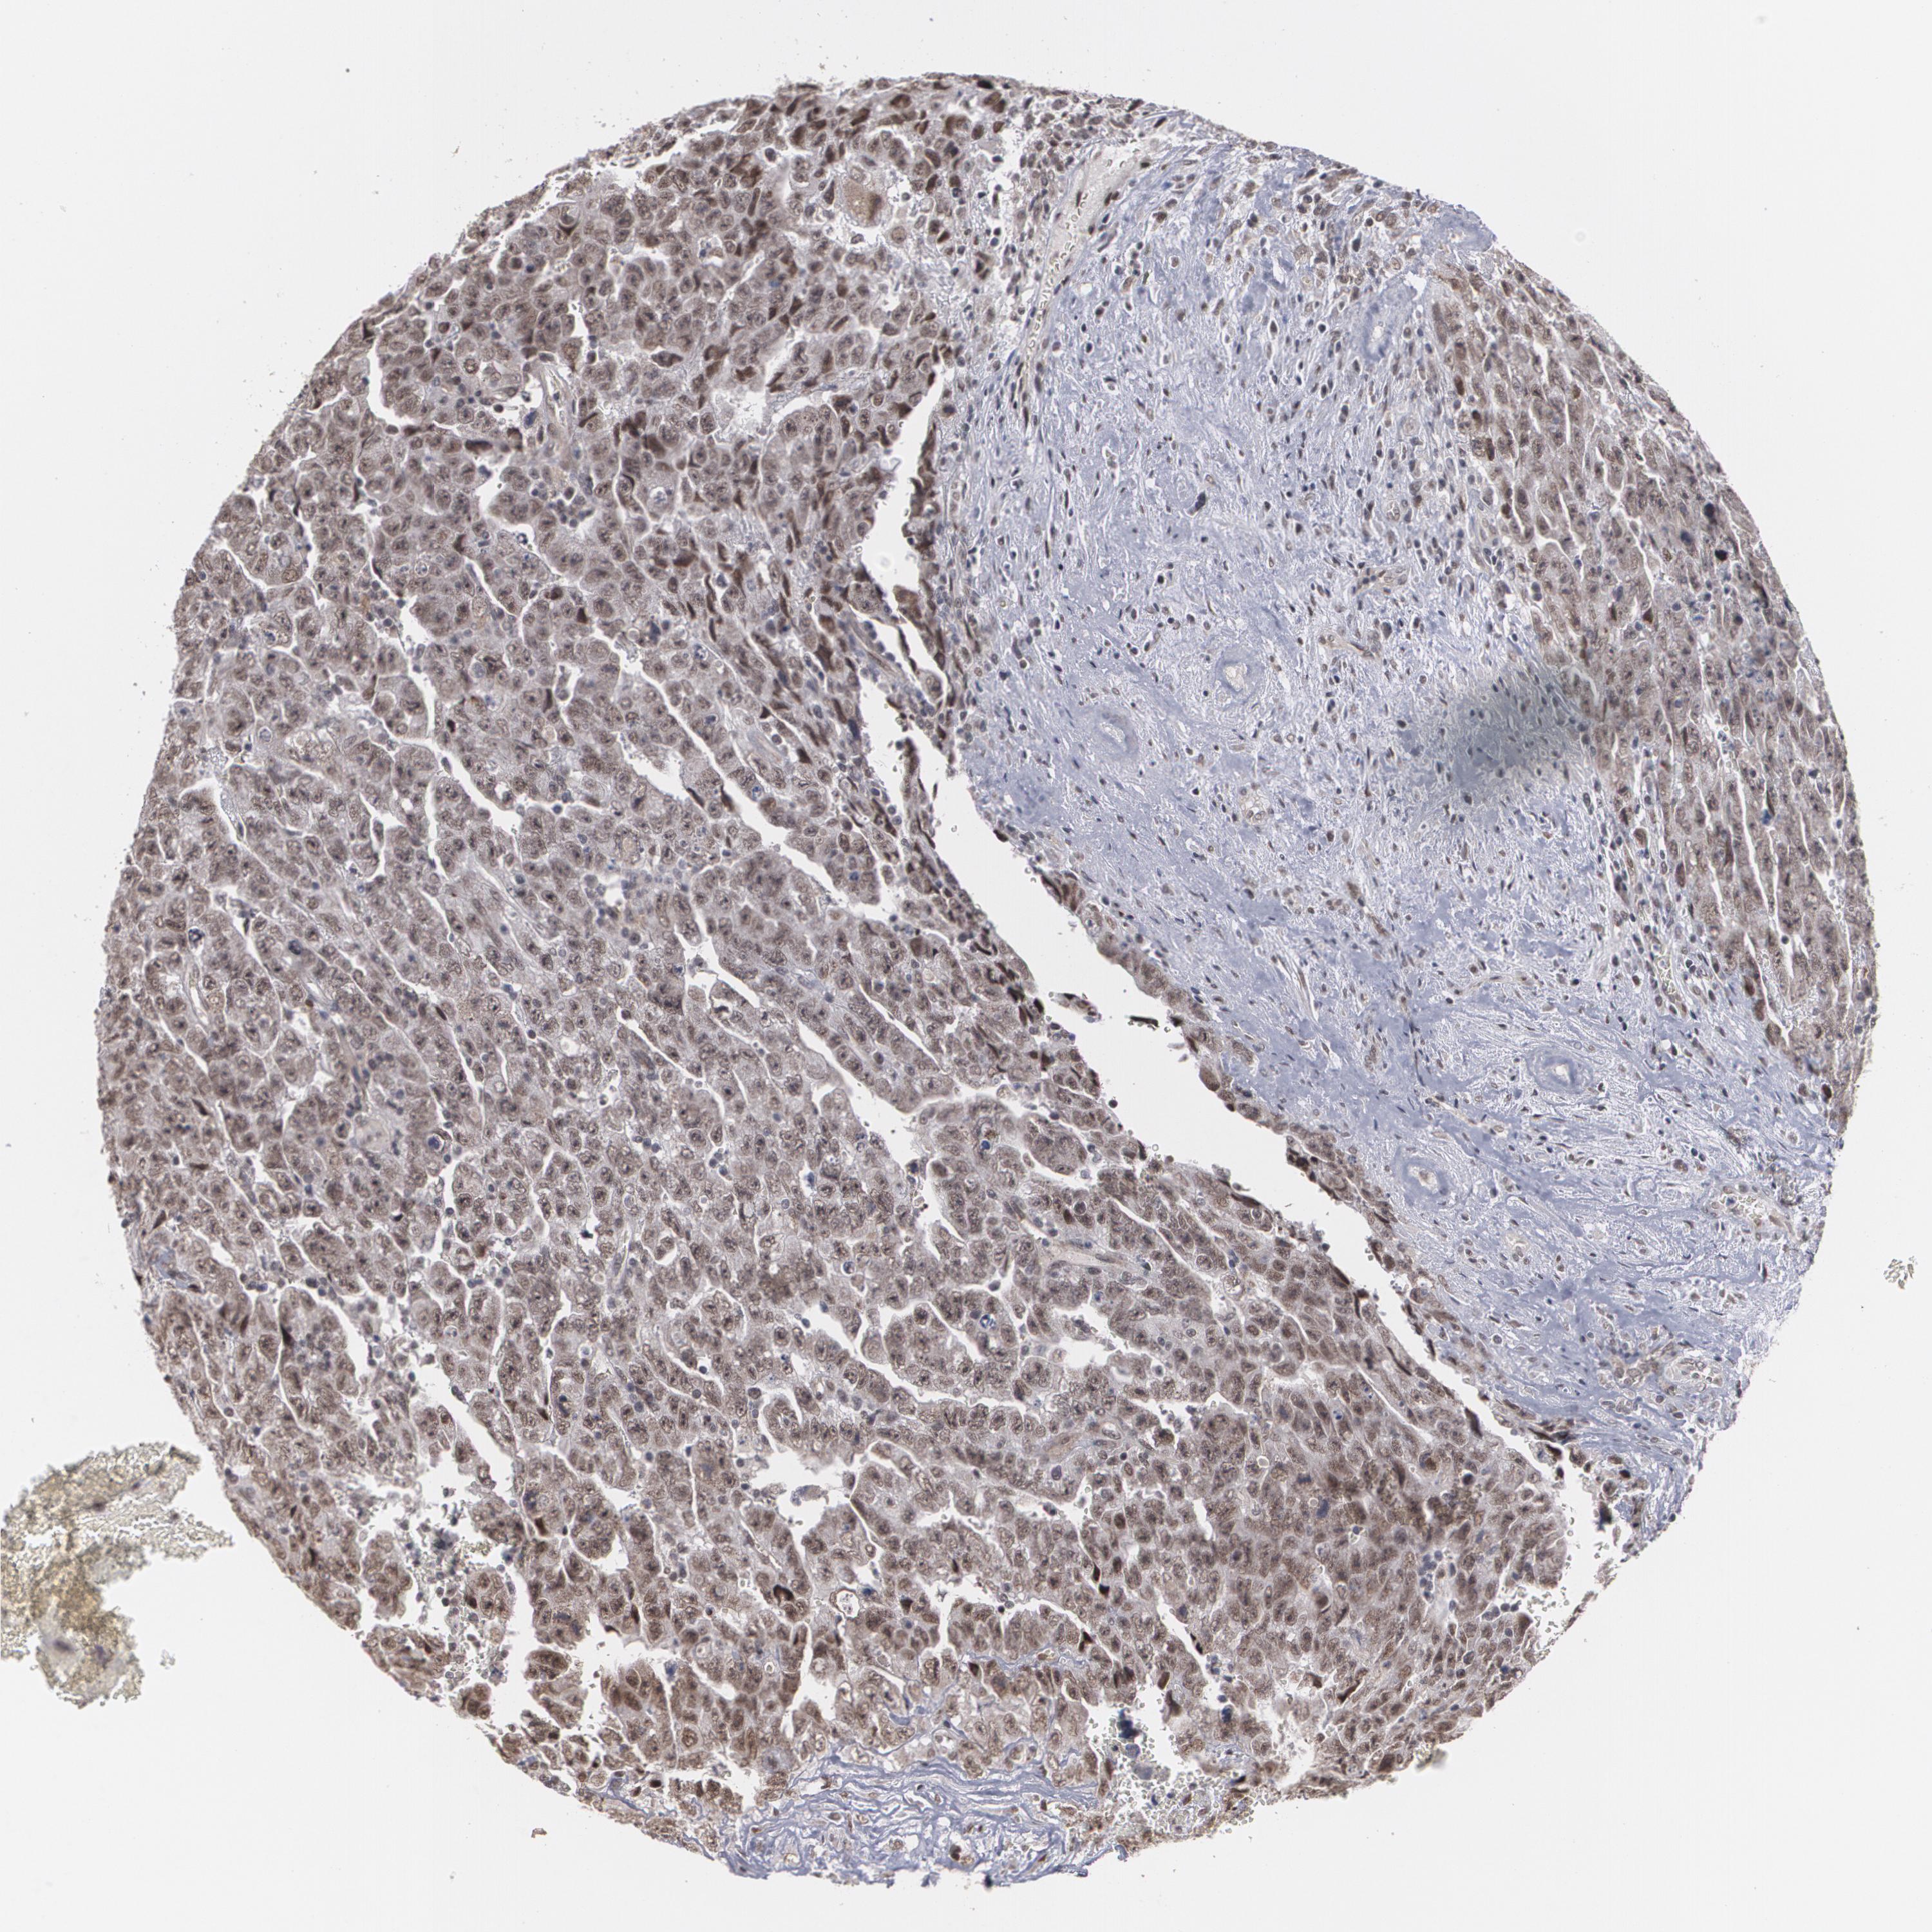

TESTIS CANCER - Protein expressioni

A mouse-over function shows sample information and annotation data. Click on an image to view it in a full screen mode. Samples can be filtered based on level of antibody staining by selecting one or several of the following categories: high, medium, low and not detected. The assay and annotation is described here.

Note that samples used for immunohistochemistry by the Human Protein Atlas do not correspond to samples in the TCGA dataset.

Antibody stainingi

Antibody staining in the annotated cell types in the current human tissue is reported as not detected, low, medium, or high, based on conventional immunohistochemistry profiling in selected tissues. This score is based on the combination of the staining intensity and fraction of stained cells.

Each image is clickable and will lead to virtual microscopy that enables deeper exploration of all samples and also displays staining intensity scores, fraction scores and subcellular localization as well as patient and tissue information for each sample.

Antibody HPA001665

Staining

High

Medium

Low

Not detected

Intensity

Strong

Moderate

Weak

Negative

Quantity

>75%

75%-25%

<25%

None

Location

Nuclear

Cytoplasmic/membranous

Cytoplasmic/membranous,nuclear

Carcinoma, Embryonal, NOS

Seminoma, NOS